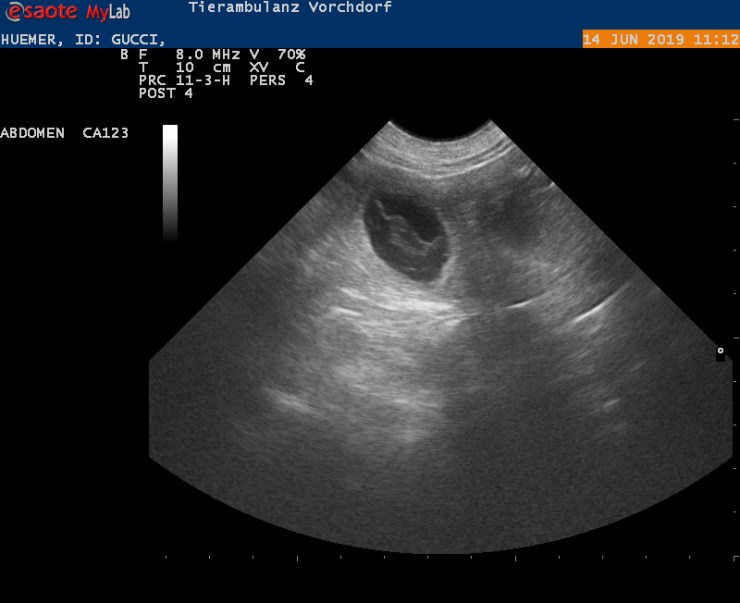

Ich freue mich jetzt auch bekanntgeben zu dürfen, dass der voraussichtliche Geburtstermin der 20. / 21. Juli sein wird.